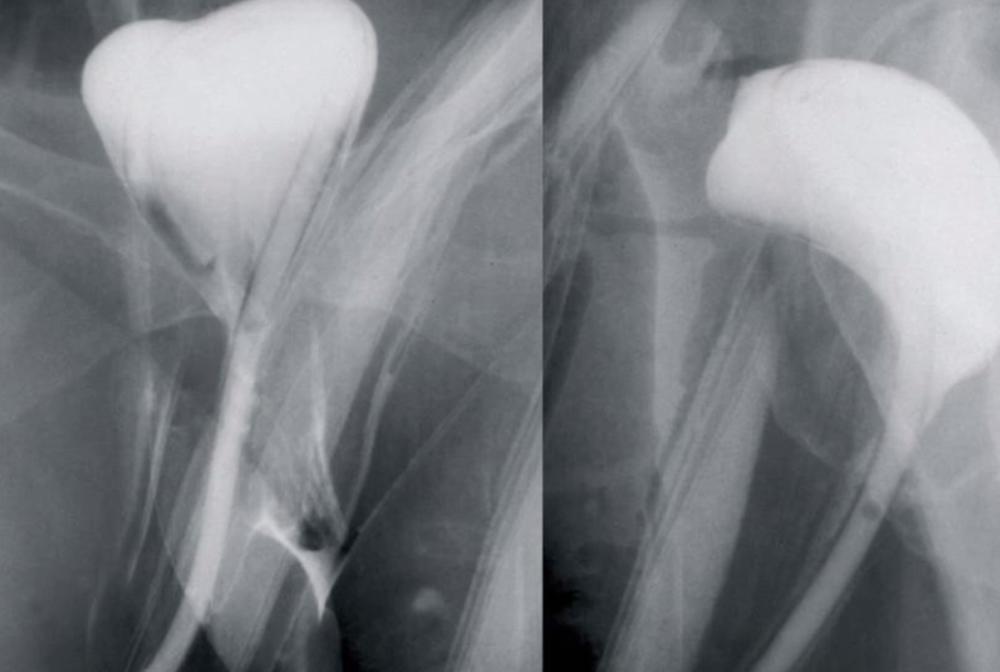

Nakon što su je iz bolnice otpustili uz tvrdnju da je sve normalno, greška lekara otkrivena je na snimku, prilikom kontrole na onkološkoj klinici, gde je otišla na hemoterapiju i zračenje. Nakon toga, morala je pod nož još čitavih 4 puta.